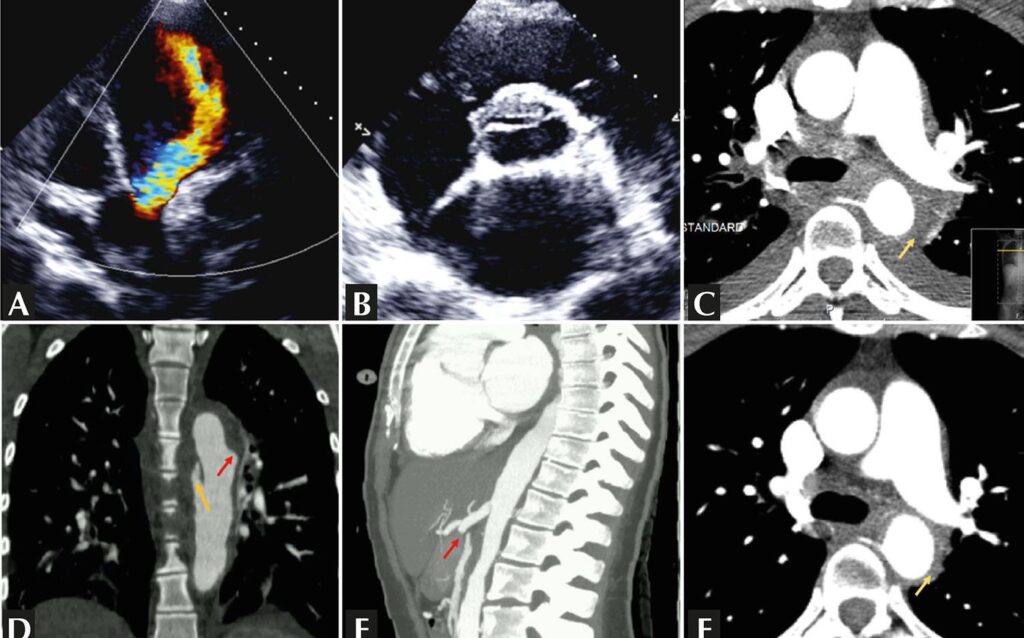

Mulher de 21 anos internada com insuficiência cardíaca e dor torácica. O ecocardiograma mostrou valva aórtica tricúspide com insuficiência importante (A), cúspide coronária direita espessada e deformada com imagem linear (B), e dilatação ventricular esquerda importante. A angiotomografia mostrou espessamento contínuo e concêntrico da parede aórtica (C), com úlcera penetrante e dissecção da aorta descendente (D), e oclusão das artérias mesentérica superior e renal esquerda (E). Presumiu-se arterite de Takayasu tipo V e iniciou-se imunossupressão com melhora significativa (F). Após remissão, a paciente foi submetida a cirurgia endovascular de aorta e troca valvar aórtica. Não se observou recidiva após um período de seguimento de 3 anos.